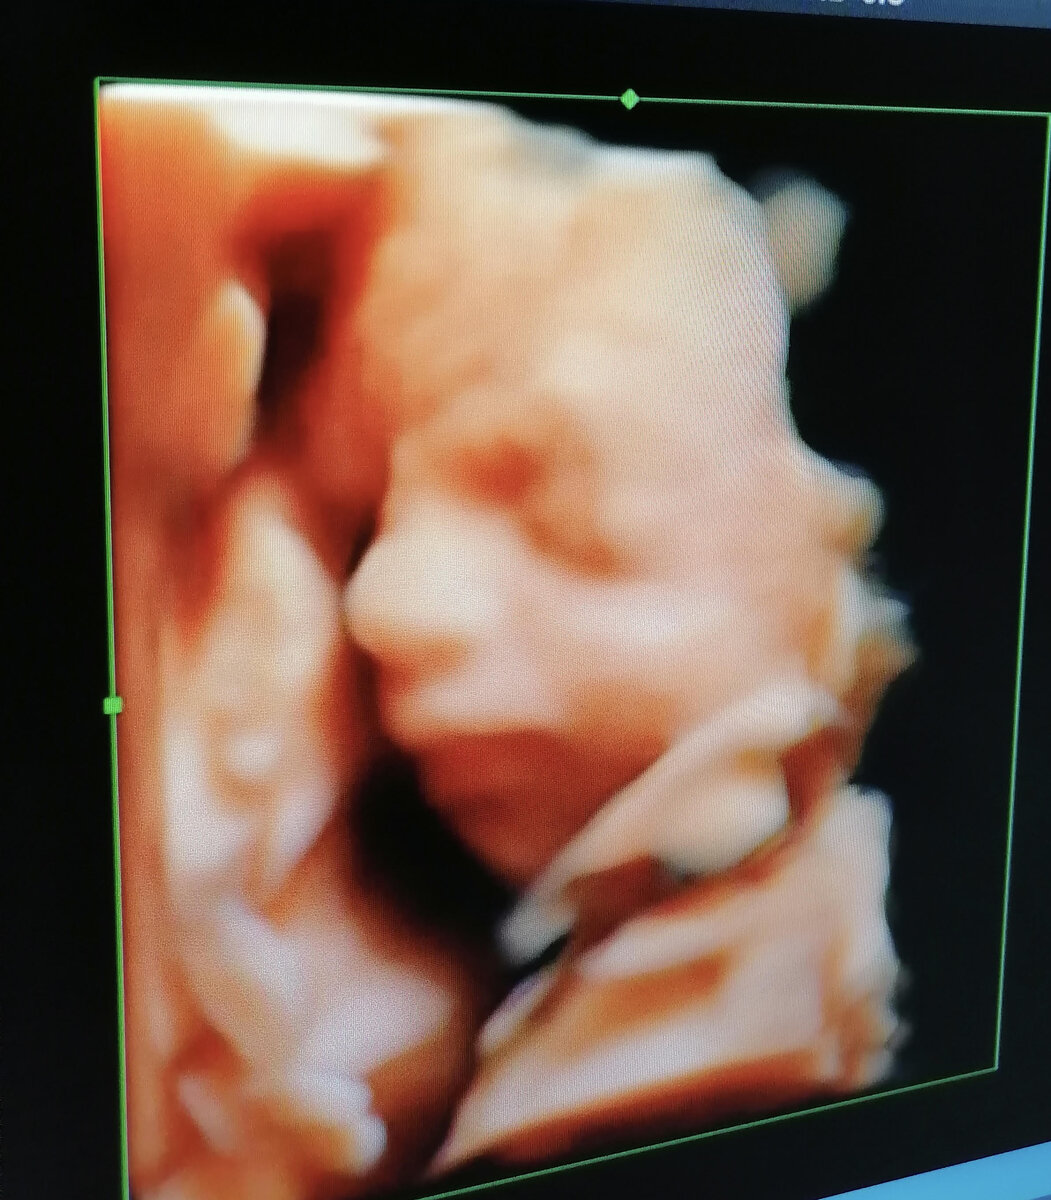

Разбирала фотографии и решила с вами поделиться. Мне как любой беременной маме конечно был интересен не только пол ребеночка, но и как выглядит малыш. Хорошо, что появилась возможность это увидеть не только в черно-белом, но и в цветном изображении. Свою малышку - дочку я старалась разглядеть от макушки до пяточек, доктор, который проводил исследование комментировал каждое действие ребенка в животе и это было наподобие экскурсии. Первое исследование я проходила в 12 недель и это было обычное черно белое узи. Это исследование считается самым важным, так как ребенок полностью сформирован к этому сроку и необходимо проверить, все ли в норме у малыша. Второе узи мы с мужем проходили в 23 недели уже в цветном изображении На фото уже хорошо видно личико и с супругом спорили чей нос, чей рот, это вообще незабываемое зрелище, когда видишь на большом экране своего ребеночка! Следующее третье узи на 33 ей неделе самое интересное, так как малышка уже подросла в животе и максимально должна быть по

23 недели

На фото уже хорошо видно личико и с супругом спорили чей нос, чей рот, это вообще незабываемое зрелище, когда видишь на большом экране своего ребеночка!